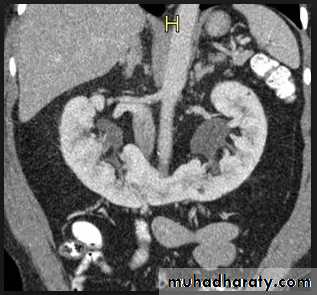

Horse shoe kidney -Kidneys may fail to separate.

-Almost invariably the lower poles remain fused.

-The kidneys axes are more parallel to the spine and malrotated.

-US, CT scan and MRI can better demonstrate the anatomy and morphology hence the diagnosis.

-PUJ obstruction and calculi formation are common .

1. The kidneys at low position .

2.Close to the spine with long axis parallel to the spine .

3. Malrotation manifested by medially directed calyces.

4- The renal pelvis and ureters are anterior and lateral in position .